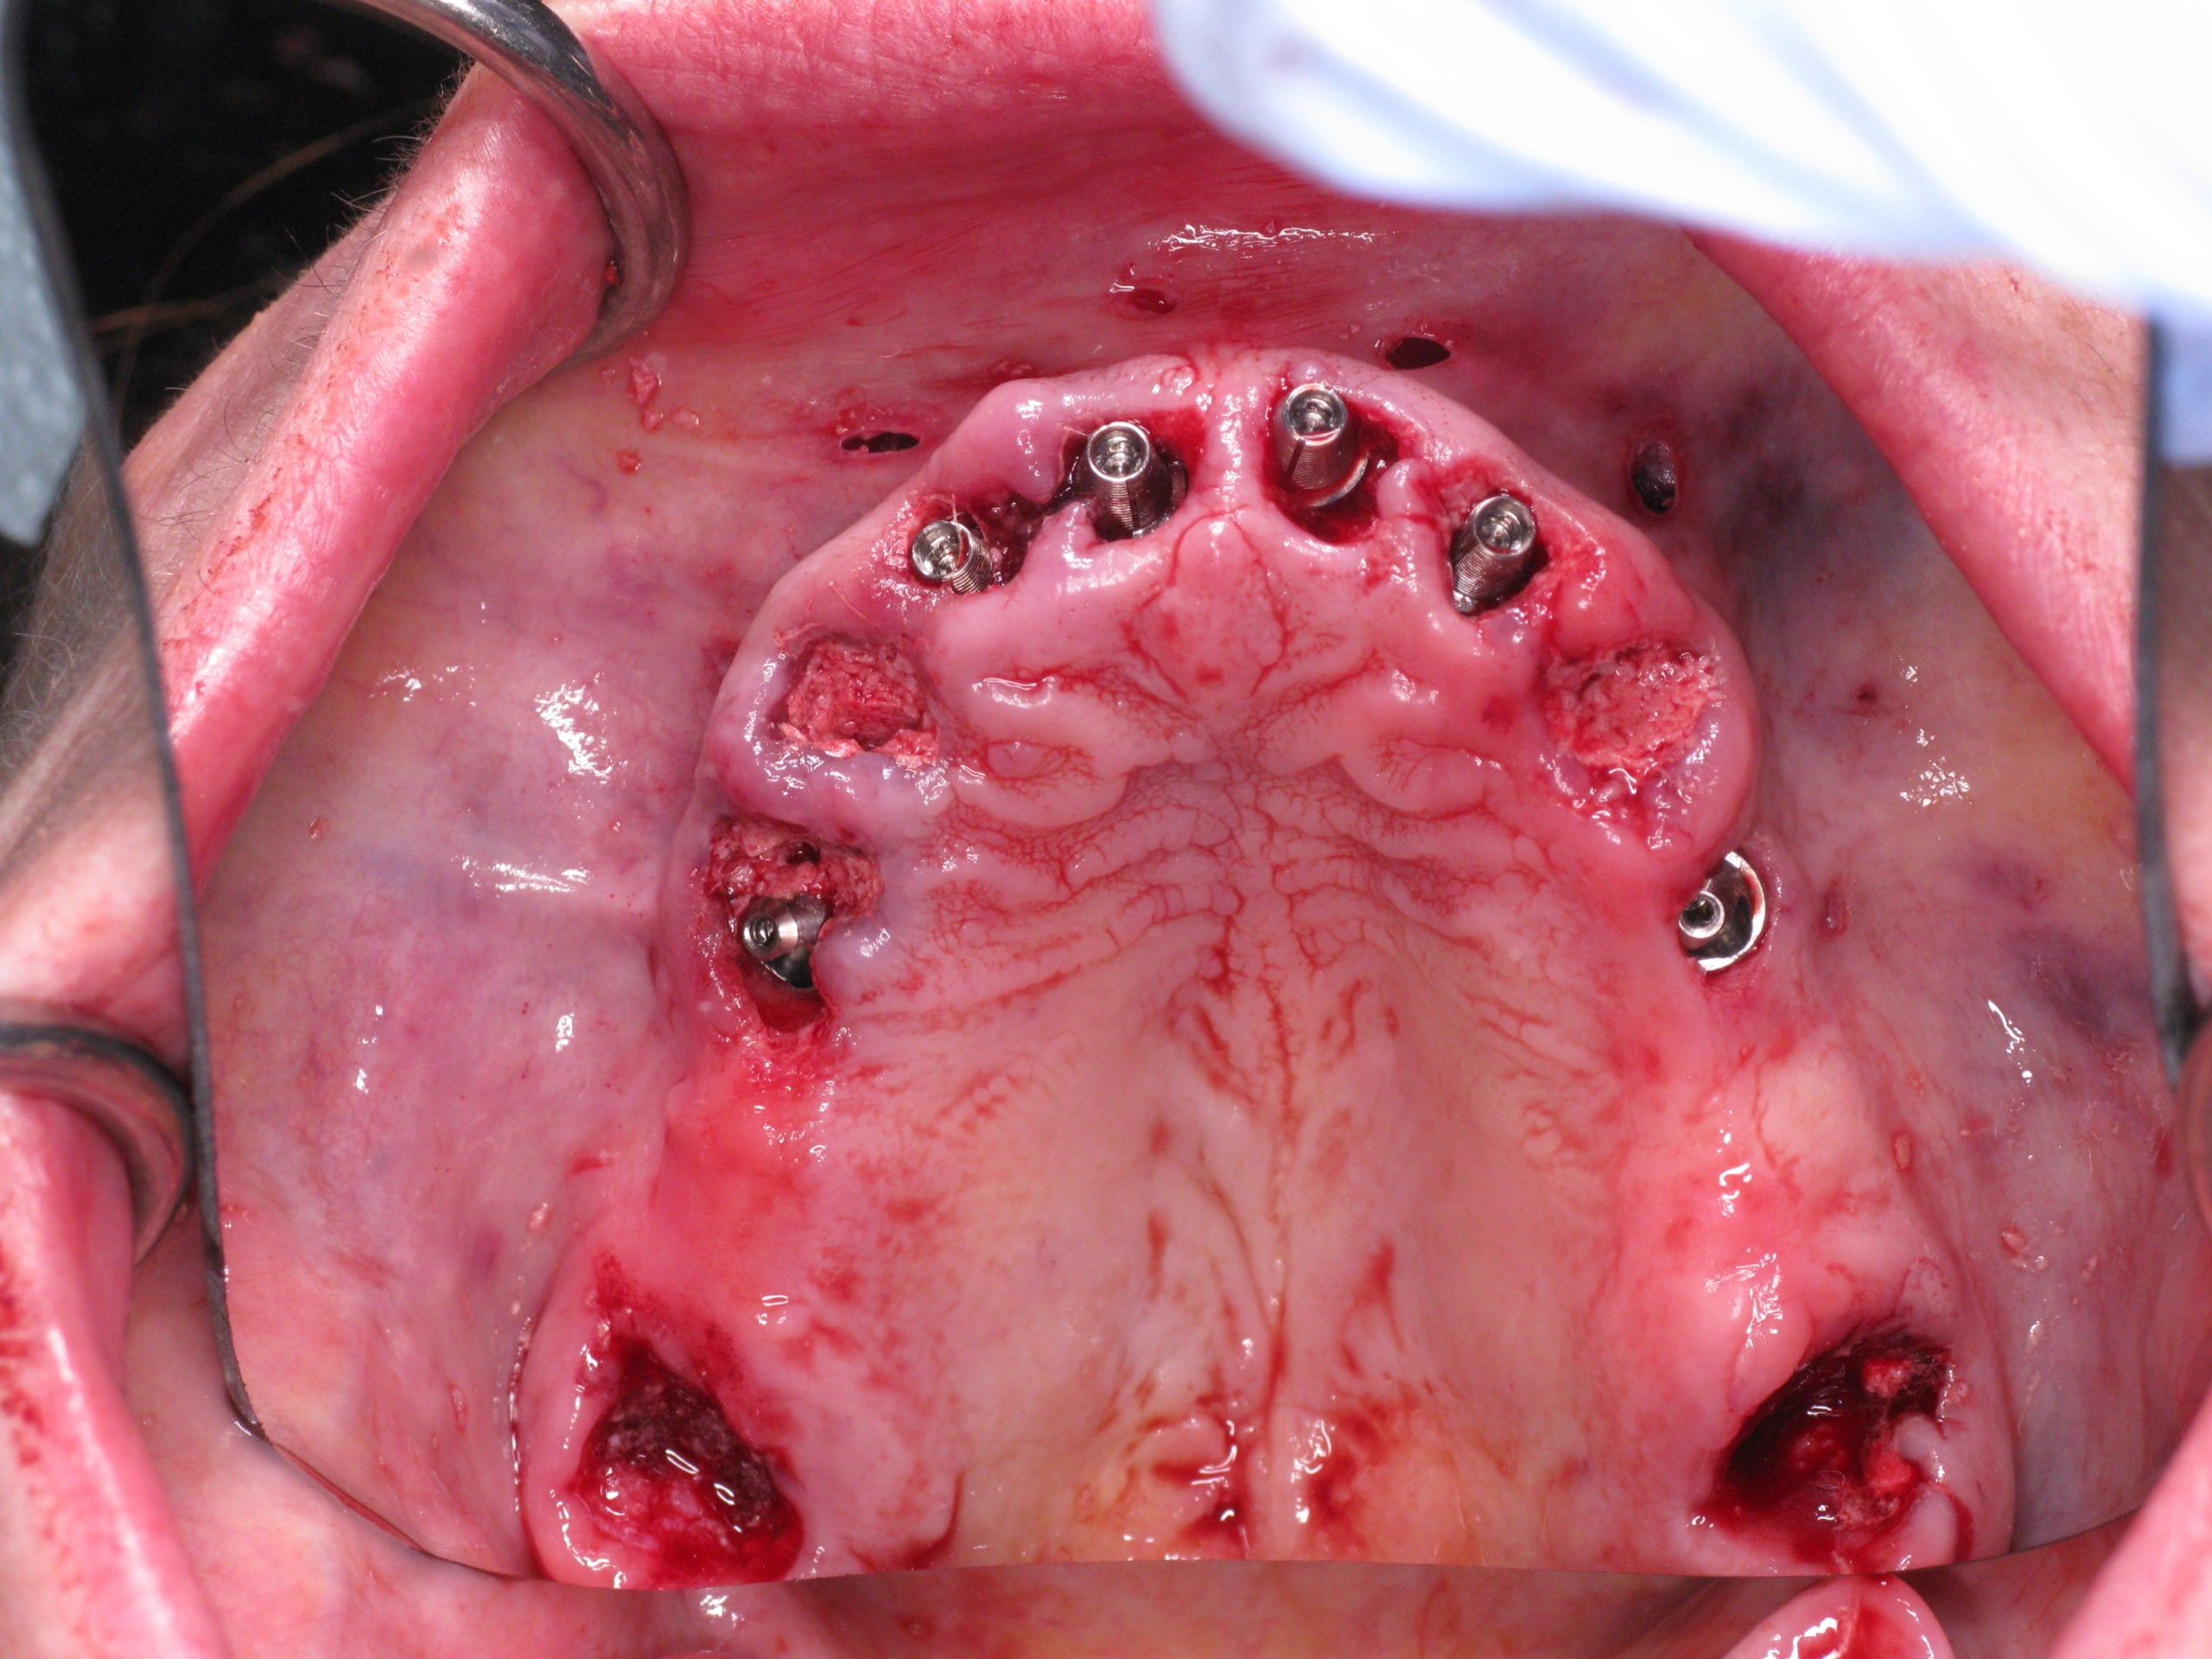

Patient presented with severe periodontal disease. Smile in a day was presented to during her consult but she was very skeptical as many people and other dentists told her this was not possible. At her initial consult she did not go through with the treatment plan. After much thought, she came back a year later and decided to go through with it and try it out. She felt no pain which was her main concern and couldn’t be happier with the results.